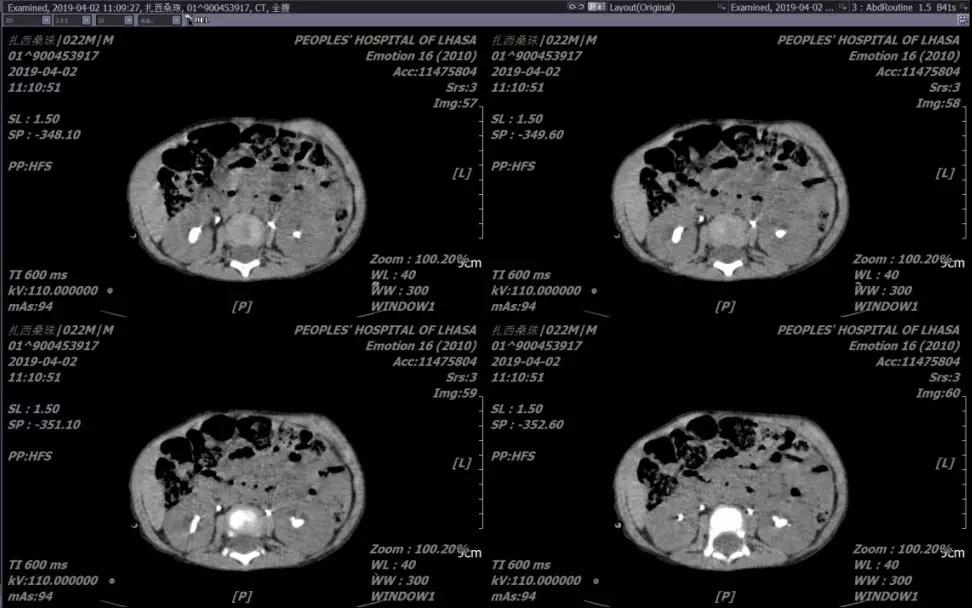

患儿,男,1岁10个月,主因“腹痛腹胀伴排尿困难1天”就诊。术前诊断:1.尿道结石;2.右输尿管结石;3.双肾结石。急诊一期予以经由尿道结石碎石术+右输尿管结石碎石术+双侧输尿管结石支架置入术。二期行mPCNL。

术后患儿愈合良好,术后第3天第4天依次拔除肾造瘘管,第5天拔除尿管出院。